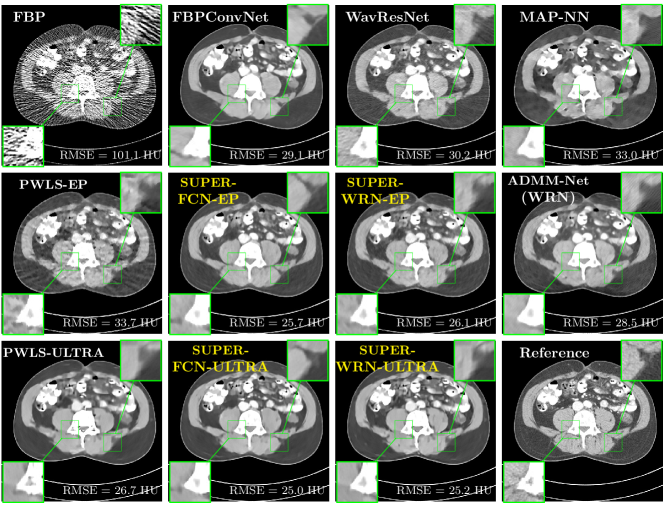

Fig. 2 shows a test example reconstructed using various methods.

Refer to caption

Figure 2: Reconstructions of slice 100 from patient L192 using various methods. The display window is [800 1200] HU.

We observe that PWLS-EP reduces the severe noise and streak artifacts observed in the low-dose FBP images, and the transform learning-based method PWLS-ULTRA further suppresses noise and reconstructs more details of the image such as the zoom-in areas. However, both methods have some blurry artifacts. The standalone FBPConvNet method heavily removes noise and streak artifacts, while introducing several artificial features (e.g., feature indicated by the arrow in the top-right box in Fig. 2). WavResNet denoises the image without introducing artifical features, but still retains some streaks around image boundaries and blurs some details (e.g., feature indicated by the arrow in the bottom-left box in Fig. 2). The state-of-the-art MAP-NN method performs slightly better than WavResNet in terms of suppressing streak artifacts, while it still loses some details as indicated in the zoomed regions. The competing plug-and-play unrolled method—ADMM-Net with WavResNet denoiser—outperforms the standalone WavResNet method, but still has some streak artifacts and blurred details. Compared to these methods, the proposed SUPER methods (SUPER-WRN-EP, SUPER-WRN-ULTRA, SUPER-FCN-EP, and SUPER-FCN-ULTRA) improve the reconstruction quality in terms of removing noise and artifacts, and recovering details more precisely. Two other example comparisons are included in the supplement (Fig. 10 and Fig. 11).